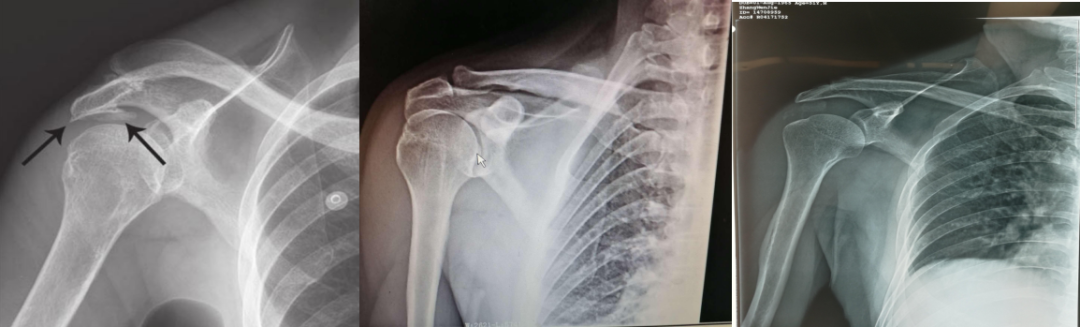

X线检查:对诊断无特异性,但有助于鉴别和排除肩关节骨折、脱位及其他骨、关节疾患;